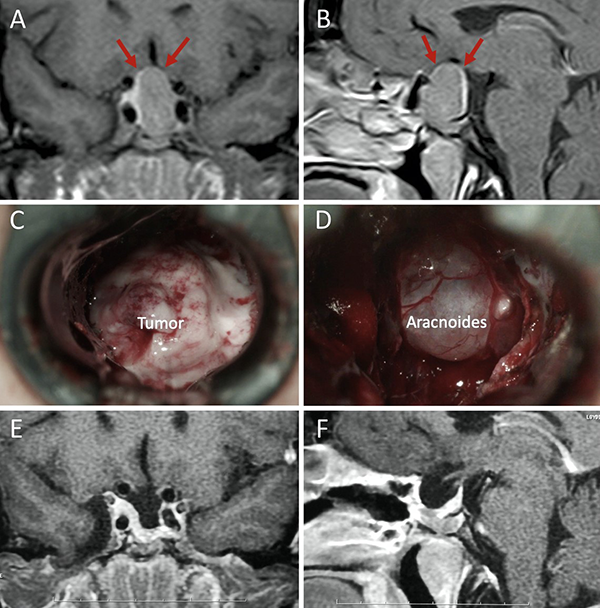

Una clasificación clásica de los adenomas es según su tamaño. Se los clasifica en microadenoma <10 mm (fig. 2), macroadenoma >10 mm (fig. 3), y adenoma gigante > 30 mm (fig. 4). Esta clasificación es importante ya que los índices de remisión están ligados al tamaño del adenoma y también su recidiva.12

Figura 3: Macroadenoma. A-B: RM preoperatoria; C-D: Campo visual preoperatorio; E-F: RM postoperatoria; G-H: Campo visual postoperatorio.

Figura 7: Barrera selar mixta. A y C) RM preoperatoria corte coronal; B y D) RM preoperatoria corte sagital; E-F) Hallazgos intraoperatorios; G-H) RM postoperatoria. Flechas y líneas: color rojo indican barrera débil; color amarillo indican barrera fuerte. Tomado deVillalonga JF, Ries-Centeno T, Sáenz A, Solari D, Cervio A, Campero A. The mixed sellar barrier: a new subtype of this novel concept. World Neurosurg. 2019;132:5-13.